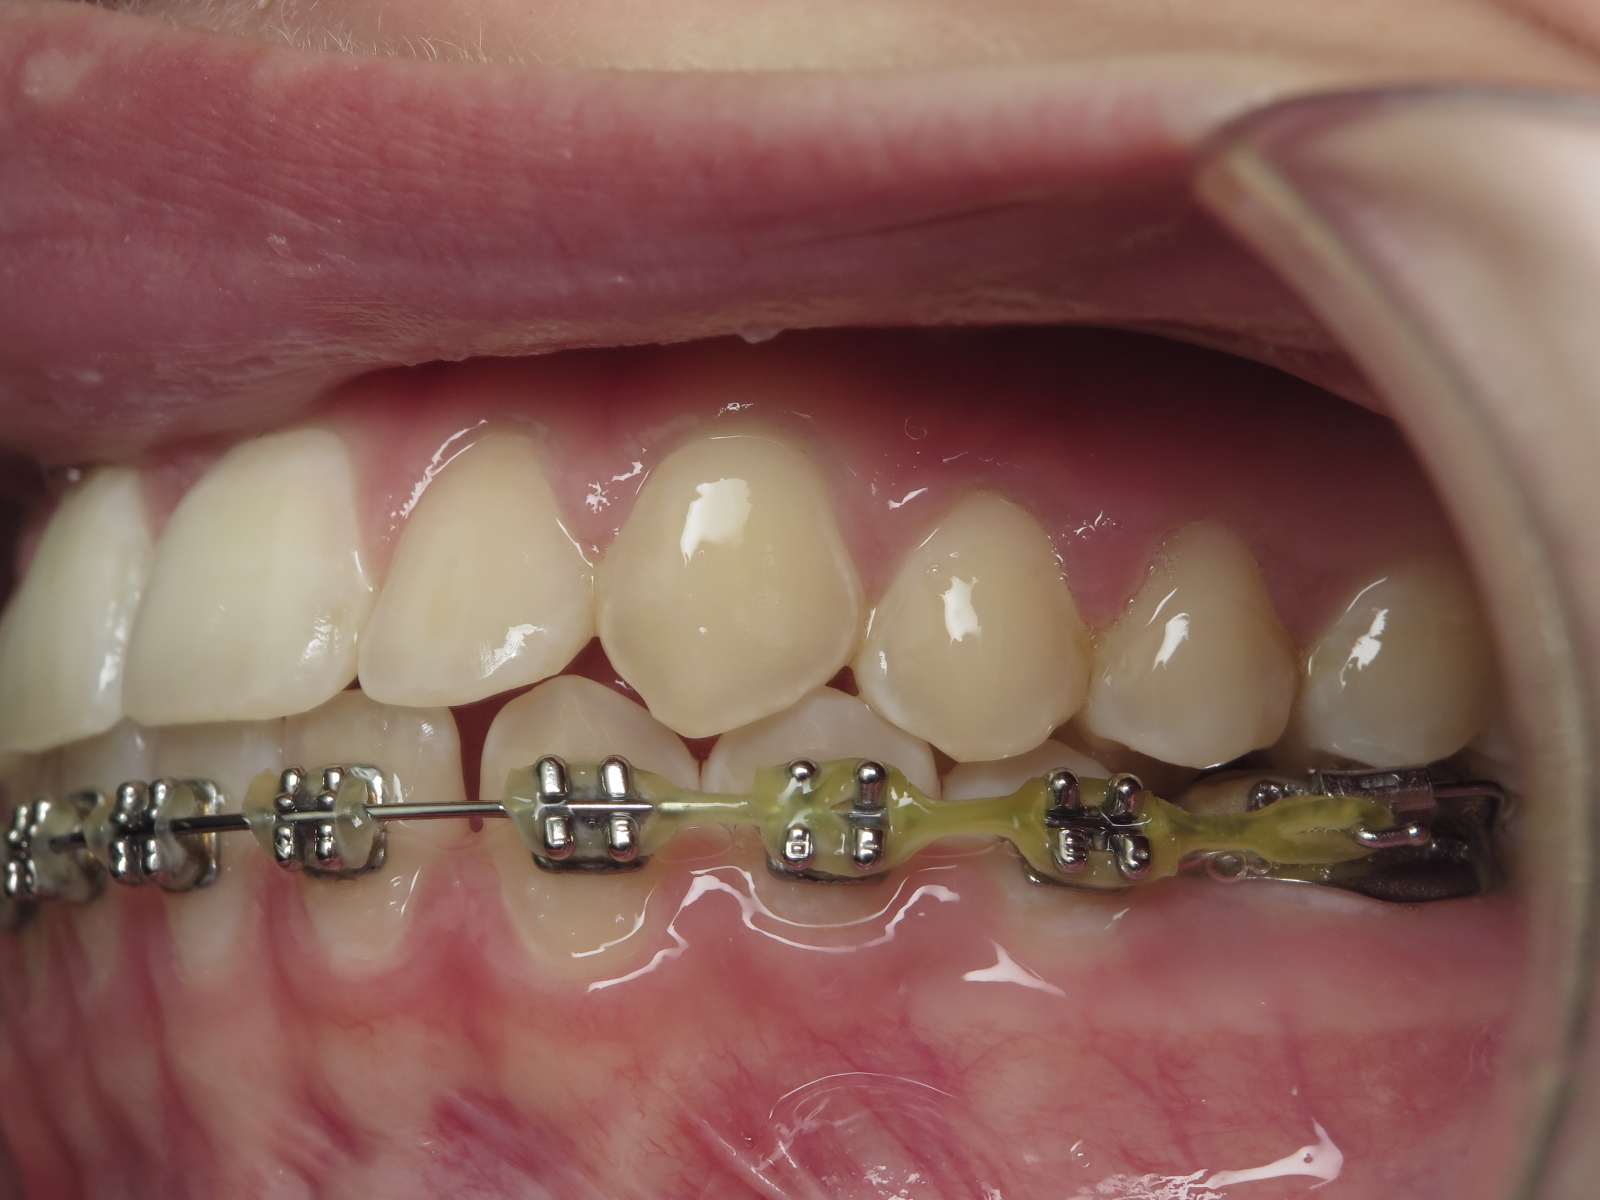

appareillage multibagues traitement en cours

bilan début et en cours de traitement